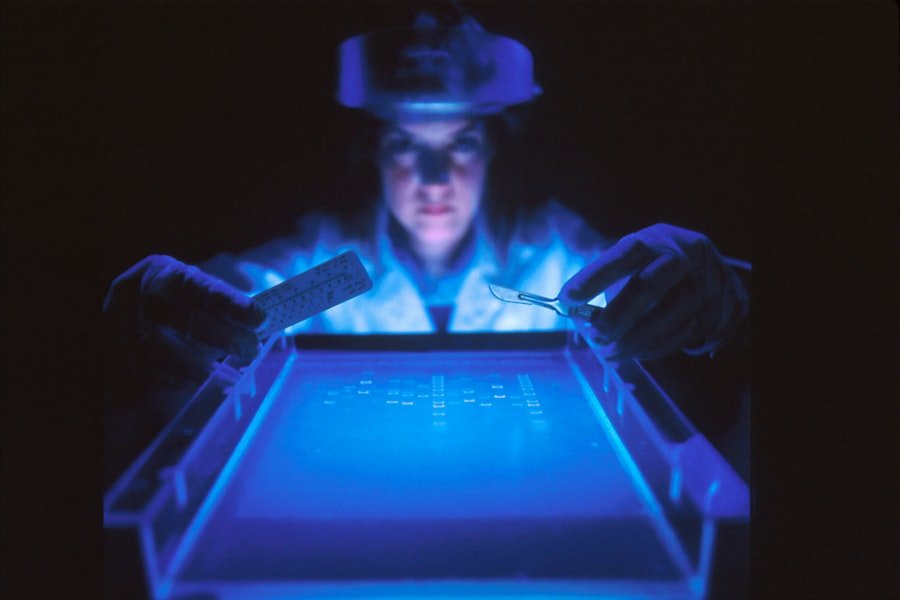

数据在医学研究和临床试验中的应用

数据还被用于支持医学研究和临床试验,以促进新药物和治疗方法的开发。通过分析大量的临床数据,科学家们能够更好地了解疾病的发病机制和治疗效果,为未来的医学进步奠定基础。